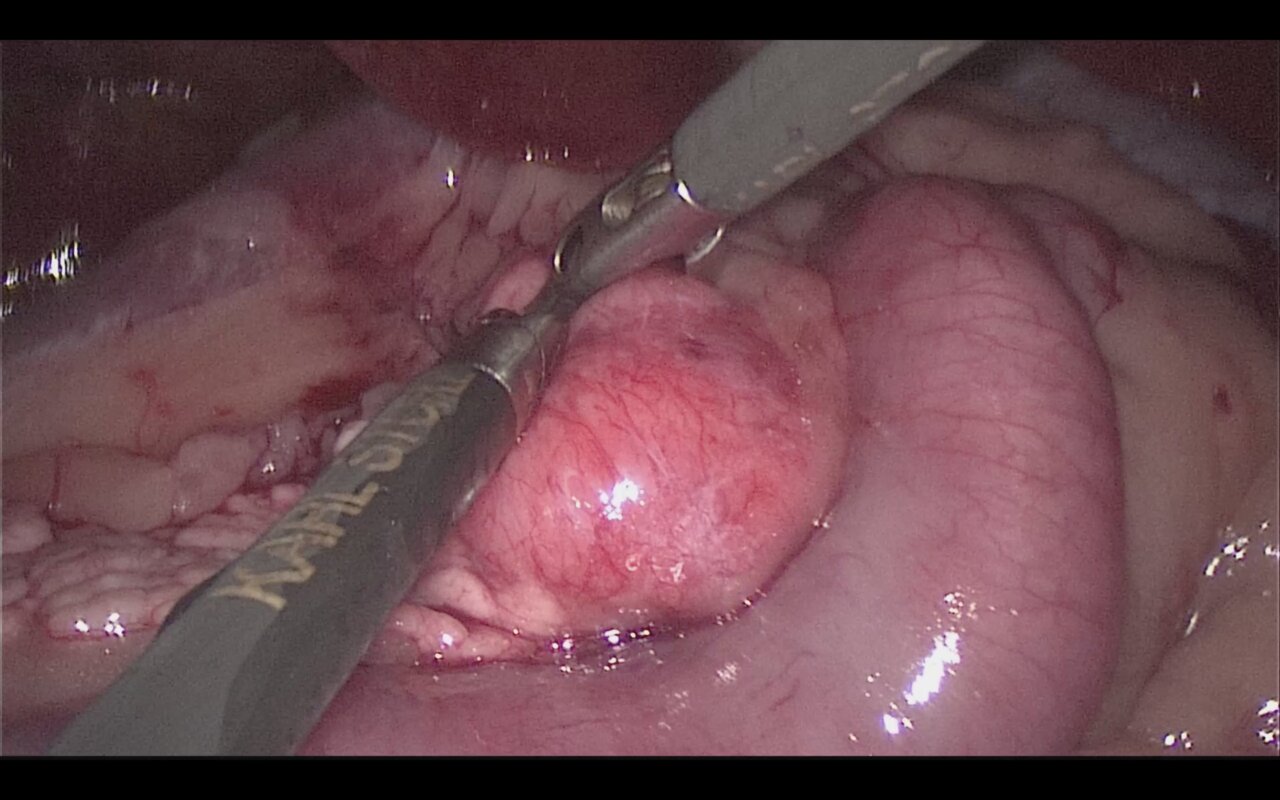

El tratamiento quirúrgico es el de elección para perros con enfermedad en estadio I (enfermedad localizada) o II (presencia de metástasis locorregional) e implica una pancreatectomía parcial para extirpar el tumor primario y cualquier metástasis visible (imágenes 4A-4K y 5A-5H). La mediana de supervivencia es más larga en los perros tratados quirúrgicamente en comparación con los perros tratados médicamente, como se describe en dos estudios donde la mediana del tiempo de supervivencia de los perros sometidos a pancreatectomía parcial fue de 381 días y 785 días, respectivamente, en comparación con 74 días y 196 días, respectivamente, en aquellos tratados solo con tratamiento médico.30 En otro estudio reciente, el tiempo medio de supervivencia registrado para 49 perros con insulinoma fue de 561 días y de hasta 746 días para perros que tuvieron resolución de hipoglucemia, con un tiempo medio euglucémico global (tiempos desde la cirugía hasta la primera detección de hipoglucemia en cualquier momento después de la cirugía) de 424 días para todos los perros.39

Imágenes 4A – 4K. Secuencia de imágenes quirúrgicas en un perro (con las imágenes del TC), durante una pancreatectomía total del lóbulo izquierdo y cuerpo del páncreas (usando la técnica de “guillotina” sutura/fractura con el nudo de Miller modificado) y resección de NNLL centinelas, por insulinoma en el cuerpo del páncreas.

Un beneficio adicional de la técnica laparoscópica para los pacientes oncológicos reside en que la rápida recuperación influye positivamente en la instauración precoz del tratamiento coadyuvante. En comparación, la cirugía mínimamente invasiva (CMI) ofrece mejor visualización, magnificación, reducción de la tasa de infección y disminución del dolor posoperatorio; ofrece una alternativa a las técnicas de pancreatectomía quirúrgica abierta en los perros, especialmente para tumores de pequeño tamaño localizados en el aspecto distal de los lóbulos pancreáticos (vídeo 1).16